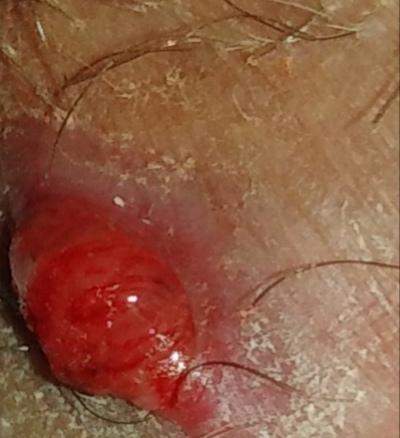

Abszess im genitalbereich frau. Ein Furunkel ist eine schmerzhafte Entzündung des Haarfollikels oder auch Haarbalg Follikulitis und eine Form des Abszesses. Eine Vulvitis ist eine Entzündung der äußeren Geschlechtsorgane der Frau. Öffnet sich der Abszess tritt Flüssigkeit oder Eiter aus.

An einem Abszess sollte man niemals herumdrücken oder ihn aufstechen. Bei der Frau hingegen kann sich ein Abszess im Bereich der Schamlippen ausbilden speziell im Bereich der Bartholin-Drüse. Gelangen die Bakterien ins Blut droht eine Blutvergiftung.

Nach höchsten wissenschaftlichen Standards verfasst und von Experten geprüft Ein Abszess ist eine Eiteransammlung die durch Bakterien verursacht wird. In selteneren Fällen kommt es zur eitrigen Einschmelzung des umliegenden Gewebes. Klingt nicht nur äußerst fies ist es auch.

Leider kamen die Abzesse immer wieder und immer wieder an einer anderen Stelle. Pilzinfektionen im Genitalbereich treten besonders häufig auf. Abszesse können beachtliche Größen erreichen bis zur Größe eines Hühnereis.

Sie sind hoch ansteckend. Es kann sich ein Abszess bilden der bis zu Hühnerei-groß ist.